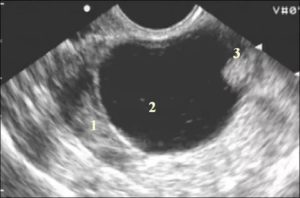

Эндометриоидная киста может наблюдаться изолированно либо в сочетании с обширным эндометриозом малого таза, который эхографически не выявляется. Средний размер эндометриоидных кист составляет 5 см, с характерным геморрагическим содержимым. Из- за последнего ее называют «шоколадной кистой».

Эндометриоидные кисты часто бывают двусторонними. При УЗИ выявляют утолщенную однокамерную кисту с наличием однородного эхопозитивного внутреннего содержимого и среднего уровня звукопроводимости.

Если из-за распространенного эндометриоза возможна облитерация дугласова пространства, матка из-за спаечного процесса может отклониться кзади.